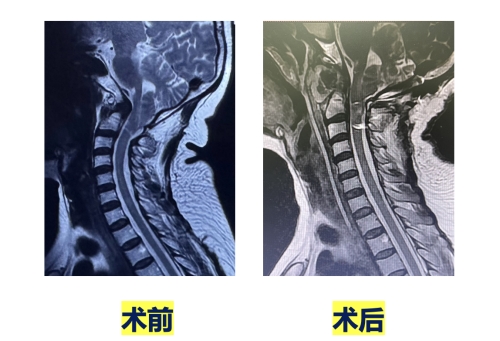

9月22日,由邓幼文主任医师、李劲松副主任医师及彭毅主治医师组成手术团队,在神经电生理监护下为罗阿姨实施手术。团队实现了寰枢关节解剖复位,切除寰椎前弓,超过齿状突的宽度,利用钉板系统强大的复位功能,使齿状突降至寰椎水平,圆满地完成了手术。术后复查影像显示:斜坡枢椎角由术前123°增大到了166°,延髓腹侧压迫完全解除。随着寰椎后弓切除,枕骨相对水平化,就如同一个簸箕兜底将其铲起,小脑扁桃体下疝明显改善。术后罗阿姨双手麻木、颈肩疼痛、行走不稳的症状得到明显缓解。罗阿姨的儿子激动地握住医务人员的手不停表达感谢。